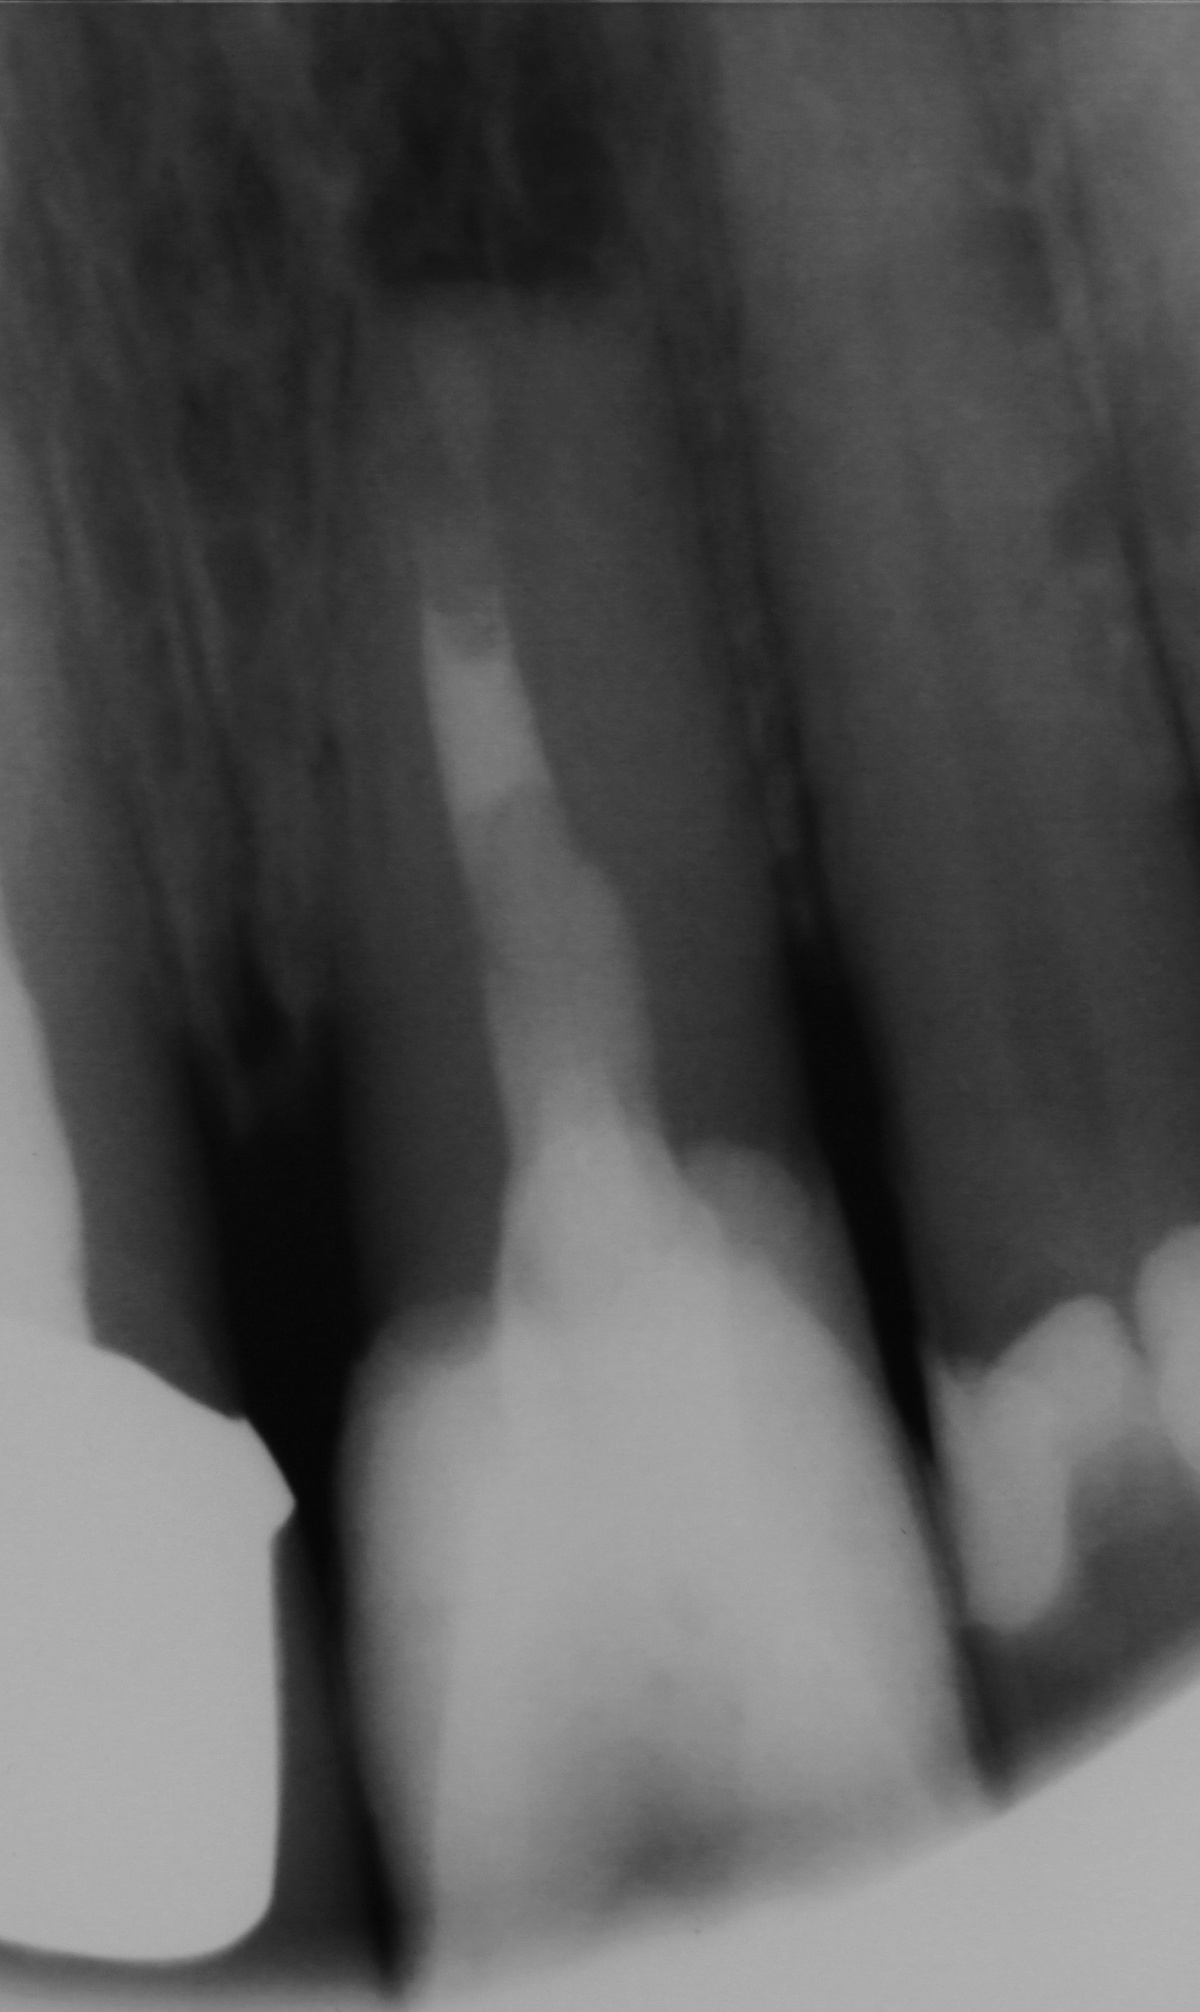

Zahn 22, zudem zeigen sich Kalzifizierungen im

Bereich des Wurzelkanaleinganges.

Eine 39-jährige Soldatin stellte sich im Januar 2020 mit Druckbeschwerden Regio 22 in unserer Abteilung vor. Wie auch in der vorangegangenen Falldarstellung konnten die Beschwerden mit Druck auf das Vestibulum verstärkt werden. Der Perkussionstest fiel deutlich positiv, der Vitalitätstest hingegen negativ aus. Eine erhöhte Lockerung des Zahnes lag, trotz des eindrucksvollen Röntgenbefundes, nicht vor. Erste Beschwerden traten laut Aussage der Patientin bereits 2014 auf. Das zu diesem Zeitpunkt angefertigte Röntgenbild zeigte keinen signifikanten pathologischen Befund, woraufhin die Situation weiterhin beobachtet wurde. Das aktuell angefertigte Röntgenbild zeigte eine umfangreiche periapikale Osteolyse, welche sich bis zu den Wurzelspitzen 21 und 23 erstreckte. Der Vitalitätstest der beiden benachbarten Zähne fiel positiv aus.